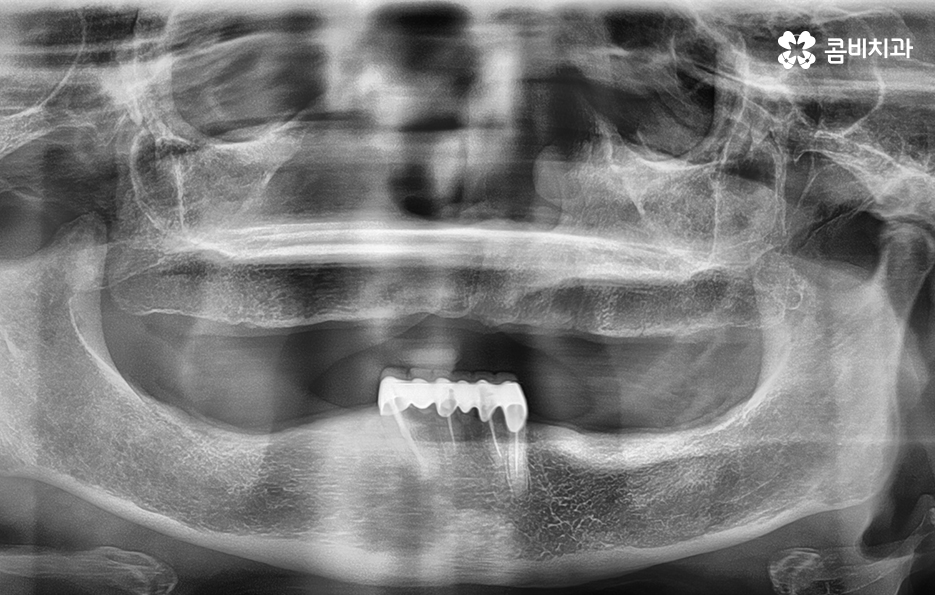

치아의 대부분이 빠지고 아랫니 브릿지만 남아 있는 상태

오늘은 65세이상임플란트에 대한 이야기를 해볼까 하는데요.

왜 '65세이상'으로 특정 지어 말씀을 드리냐면

건강보험에서 본인 부담금의 혜택이 시작되는 나이이기 때문입니다.

아랫니는 잇몸이 주저 앉은 상태이며 위의 잇몸과 잇몸뼈의 상태는 비교적 양호한 편